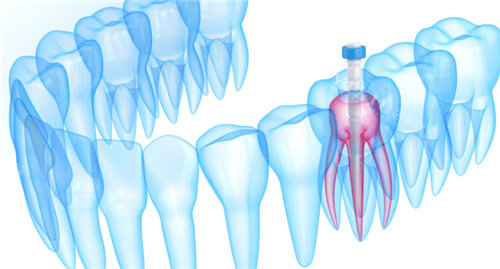

牙齿根管治疗:976 元起

根管治疗清理牙髓:426 元起